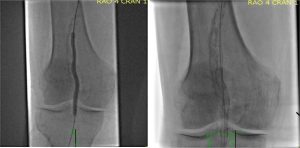

Catheter based interventions for pulmonary embolism is on the rise. The rise in mainly in patients who present with submassive PE. The intent of intervention is to reduce clot burden. This is done to improve acute symptoms and to reduce long-term complications. A common intervention for pulmonary embolism is infusion of thrombolytics. This can be…